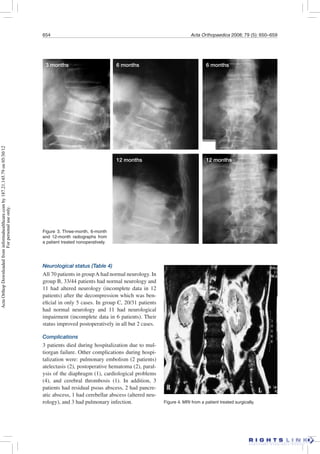

Figure 3. Three-month, 6-month

and 12-month radiographs from

a patient treated nonoperatively.

3 months 6 months 6 months

12 months 12 months